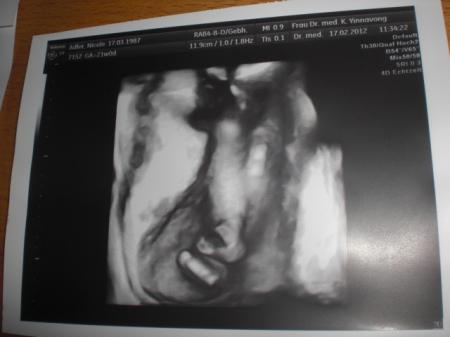

Hallo ihr lieben, nun melde ich mich endlich zurück! Ich war ja ein paar wochen nicht hier da ich umgezogen bin! Ich fass mich kurz versprochen! Also die Wohnung ist super schön das Kinderzimmer ist noch nicht eingerichtet aber zumindest stehen die babysachen vom großen schonmal da wo sie hingehören;) So und nun eine schöne Nachricht ich war vergangenen Freitag bei der feindiagnostik und was soll ich sagen.... Es wird ein Mädchen, sie ist gesund und munter und wog letzte woche noch ca. 400g! Nun heute hab ich die 23.Woche erreicht und es sind noch 17 lange die vor mir liegen! Bilder folgen sind echt schön geworden! Nun zu meiner Frage, wie sieht das bei euch aus, wieviel habt ihr bisher zugenommen? Also ich bin jetzt bei 6kg mehr Und ihr, bin echt neugierig was euer schnitt ist! Freu mich schon auf eure Antworten und hoffe es motiviert mich das es vielleicht nicht soviel ist wie ich glaube, ich komm mir ziemlich fett vor! Bauchbild ist von heute

ich hoffe ihr könnt es erkennen?